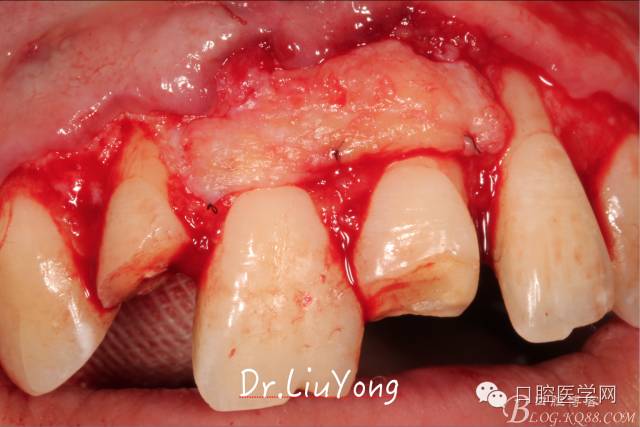

系帶手術(shù)后兩周,進(jìn)行上頜前牙唇側(cè)的牙齦退縮的手術(shù)治療,由于局部附著齦缺如及牙齦厚度不足,因此同期進(jìn)行上皮下結(jié)締組織移植,解決附著齦及牙齦厚度不足的問題。

術(shù)中,可見明顯的唇側(cè)骨開裂,如上圖: